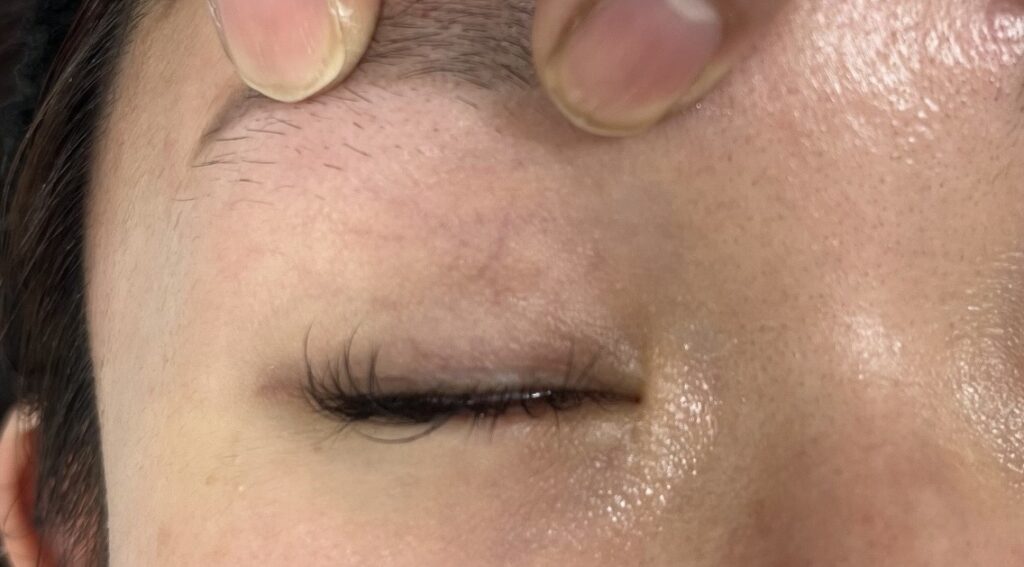

実際取り出した埋没糸。1つ目の糸は、瞼板・挙筋腱膜・皮膚眼輪筋を通糸されており、スルっと抜けました。しかし2つ目の糸は、周辺組織との癒着が強かったため、千切れてしまいました。